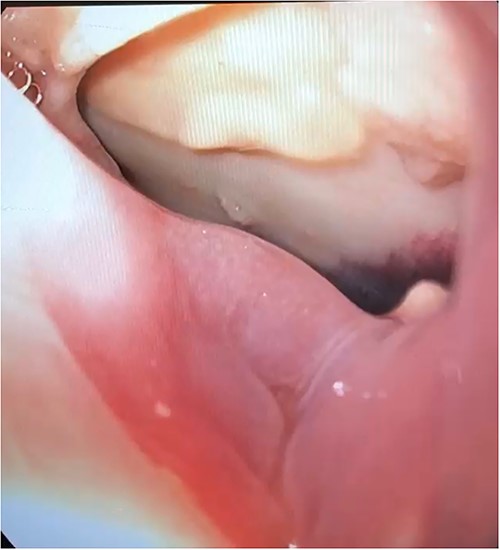

A 63-year-old man developed chest pain and fevers 3 days after left atrial ablation for paroxysmal atrial fibrillation and was readmitted. Computed tomography (CT) angiography at that time showed loculated fluid along the right lateral margin of the distal esophagus and a small pericardial effusion. He was treated for presumed pneumonia and discharged after 3 days. Over the following 2 weeks, he developed progressive dysphagia and persistent chest pain. Subsequent evaluation with a CT scan of the chest demonstrated pneumopericardium and a large pericardial effusion concerning for fistula formation. He was transferred to our institution 11 days after initial presentation for definitive management. Upon arrival to the cardiac intensive care unit (ICU), the patient was awake and alert, normotensive, but tachycardic. He was evaluated by both cardiac and thoracic surgery and taken emergently to the operating room (OR) for an exploratory thoracotomy, at which point he went into cardiac arrest and an emergent sternotomy was performed. Upon entering the chest, 1 L of purulent pericardial fluid and succus was drained, and the patient was placed on cardiopulmonary bypass (CPB). Examination of the heart demonstrated no injury; however, a fistula was identified posteriorly in the pericardium that communicated with the esophagus. An upper endoscopy was performed, and a 3 cm anterior perforation was visualized (Fig. 1). Given the instability of the patient, repair was deferred, and his mediastinum was widely drained. The patient could not be weaned from CPB due to hemodynamic instability and he was placed on veno-arterial extracorporeal membrane oxygenation with his chest left open and packed. Overnight, the patient developed fixed and dilated pupils. A non-contrast CT of the brain demonstrated infratentorial herniation and the patient was transitioned to comfort care and later expired.